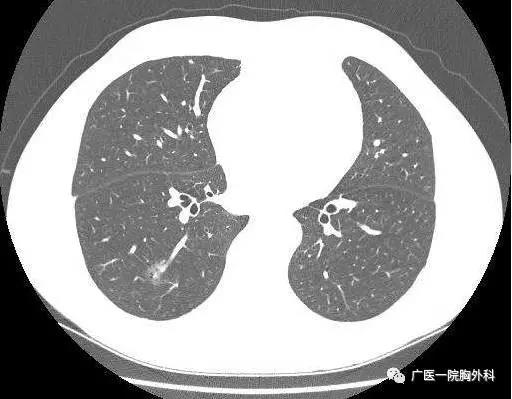

早期肺癌筛查现在最有效的手段是低剂量螺旋CT胸部平扫。那么很多人就要问了,什么是低剂量螺旋CT?他和我们每年体检中做的X光胸片有什么不一样?今天,小编就与大家一起解答肺癌筛查中大家比较经常问的几个问题吧。

目前,低剂量螺旋CT检查已成为肺癌筛查和早期诊断最常用的临床工具。首先,CT较常规胸片敏感。早期肺癌行动计划(ELCAP)研究发现,CT所发现的Ⅰ期肺癌是胸片的6倍。其次,CT检查无创、快捷,目前技术条件下,患者屏息数秒即可完成胸部扫描,放射剂量仅为3.3毫西弗,相当于一个人全年自然环境放射总量。不仅如此,随着技术进步,CT检查的放射剂量有可能进一步降低。

国际早期肺癌行动计划(I-ELCAP)所发现的肺癌,Ⅰ期肺癌占80%以上,接受手术的I期患者,十年生存率92%,因此可以认为,LDCT普查可以发现能够治愈的肺癌,推测年度LDCT筛查可以减少80%的肺癌死亡。